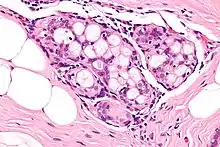

Collagenous spherulosis is characterized by a tubular/cribriform architecture with intratubular eosinophilic material that classically is arranged like the spokes of a wheel ("radial spikes"). There is usually no mitotic activity, and two cells populations (epithelial & myoepithelial) are present, like in benign breast glands.

The lesions are typically small (less than 50 spherules per lesion, less than 100 micrometers in size) and may be multifocal.

Intermed. mag.